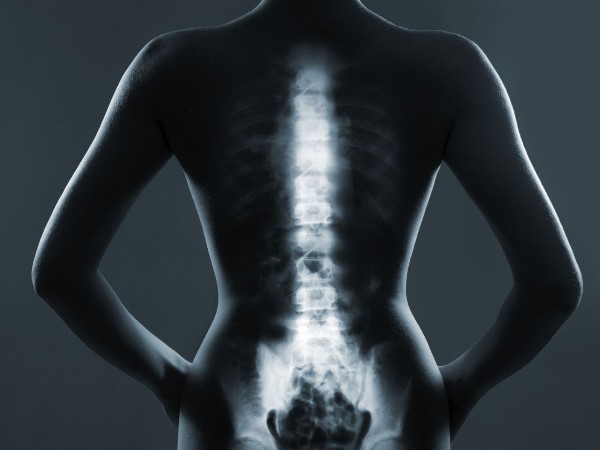

തൈറോയിഡ് ഗ്രന്ഥിയുടെയും  അസ്ഥികളുടെയും ആരോഗ്യം തമ്മില്‍ ബന്ധമുണ്ടെന്ന് നിങ്ങള്‍ക്കറിയാമോ? നമ്മളില്‍ മിക്കവരും മനസ്സിലാക്കുന്നതിലും അപ്പുറമാണ് അവ തമ്മിലുള്ള ബന്ധം. പല സ്ത്രീകള്‍ക്കും, പ്രത്യേകിച്ച് പ്രായമാകുമ്പോള്‍, തൈറോയ്ഡ് പ്രശ്‌നങ്ങളും അസ്ഥികളുടെ ബലക്കുറവും പലപ്പോഴും ഉണ്ടാകുന്നു. അതിശയിപ്പിക്കുന്ന കാര്യമെന്തെന്നാല്‍ തൈറോയ്ഡ് ഗ്രന്ഥിക്കുണ്ടാകുന്ന പ്രശ്‌നങ്ങളില്‍ നിന്ന് മാത്രമല്ല അപകടസാധ്യത വരുന്നത്, മറിച്ച് നമ്മള്‍ അതിനെ എങ്ങനെ കൈകാര്യം ചെയ്യുന്നു എന്നതിനെ ആശ്രയിച്ചിരിക്കുന്നു എന്നതാണ്.

തൈറോയ്ഡ് ഗ്രന്ഥി ആവശ്യത്തിന് തൈറോയ്ഡ് ഹോര്‍മോണുകള്‍ ഉത്പാദിപ്പിക്കാത്തപ്പോഴാണ് ഹൈപ്പോതൈറോയിഡിസം ഉണ്ടാകുന്നത്. ഈ ഹോര്‍മോണുകള്‍ ഉപാപചയം, ഊര്‍ജ്ജ നില, ഹൃദയമിടിപ്പ് എന്നിവ നിയന്ത്രിക്കുന്നു. അളവ് വളരെ കുറയുമ്പോള്‍, ശരീരത്തിലെ എല്ലാം മന്ദഗതിയിലാകുന്നു, അസ്ഥികളുടെ ആരോഗ്യം ഉള്‍പ്പെടെ. വാസ്തവത്തില്‍, ചികിത്സിക്കാത്ത ഹൈപ്പോതൈറോയിഡിസം നേരിട്ട് അസ്ഥി നഷ്ടത്തിന് കാരണമാകില്ല. ജേണല്‍ ഓഫ് ക്ലിനിക്കല്‍ എന്‍ഡോക്രൈനോളജി ആന്‍ഡ് മെറ്റബോളിസത്തിലെ ഒരു പഠന പ്രകാരം സാധാരണ പരിധിക്കുള്ളില്‍ തൈറോയ്ഡ് ഹോര്‍മോണുകളുടെ അളവില്‍ നേരിയ വര്‍ദ്ധനവ് പോലും അസ്ഥികളുടെ സാന്ദ്രത കുറയ്ക്കുകയും ആര്‍ത്തവവിരാമം കഴിഞ്ഞ സ്ത്രീകളില്‍ ഒടിവുകള്‍ ഉണ്ടാകാനുള്ള സാധ്യത വര്‍ദ്ധിപ്പിക്കുകയും ചെയ്യും എന്നാണ്.

ഹൈപ്പോതൈറോയിഡിസത്തില്‍ നിന്നല്ല, മറിച്ച് അതിന്റെ ചികിത്സയില്‍ നിന്നാണ്, പ്രധാനമായും ഹോര്‍മോണ്‍ റീപ്ലേസ്മെന്റ് തെറാപ്പി (ഒഞഠ) യില്‍ നിന്നാണ് അപകടസാധ്യത. ഹൈപ്പോതൈറോയിഡിസമുള്ള മിക്ക ആളുകള്‍ക്കും സാധാരണ ഹോര്‍മോണ്‍ അളവ് പുനഃസ്ഥാപിക്കാന്‍ സഹായിക്കുന്ന ഒരു സിന്തറ്റിക് തൈറോയ്ഡ് ഹോര്‍മോണായ ലെവോതൈറോക്‌സിന്‍ നിര്‍ദ്ദേശിക്കാറുണ്ട്. എന്നിരുന്നാലും, ഡോസ് വളരെ കൂടുതലാകുമ്പോഴാണ് പ്രശ്‌നങ്ങള്‍ ഉണ്ടാകുന്നത്.

ഇത് തൈറോയ്ഡ്-സ്റ്റിമുലേറ്റിംഗ് ഹോര്‍മോണിന്റെ (TSH) അളവ് അടിച്ചമര്‍ത്തുകയും ശരീരത്തെ ഹൈപ്പര്‍തൈറോയിഡിസത്തിന് സമാനമായ ഒരു അവസ്ഥയിലേക്ക് തള്ളിവിടുകയും ചെയ്യും. ഇത് അസ്ഥികളുടെ സാന്ദ്രത കുറയ്ക്കുകയും അസ്ഥികളെ ദുര്‍ബലപ്പെടുത്തുന്ന ഒരു അവസ്ഥയിലെത്തിക്കുകയും ചെയ്യും.